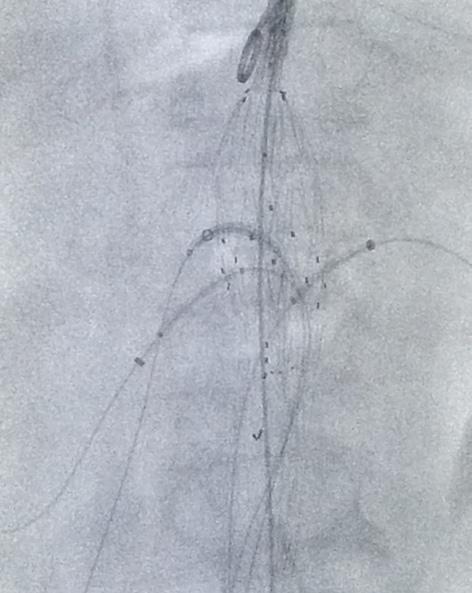

fenestrated and branched devices anatomies can be treated and repaired that were previously off-limits to both open and endovascular intervention. While these methods may involve higher rates of reintervention compared to open repair, they do not significantly affect longterm survival, making them a viable option for many patients facing aortic aneurysms or dissections. (Figure 01)

endovascular treatment stood a chance against this gold standard treatment. Low and behold, the CERAB procedure, known as Covered Endovascular Reconstruction of the Aortic Bifurcation, entered the field and has replaced the traditional bypass surgery in many cases. This minimally invasive procedure involves the use of covered stents to reconstruct the aortic bifurcation without the significant morbidities associated with laparotomy, graft infection, graft-enteric fistula and incisional hernias or bowel obstruction. (Figure 02)